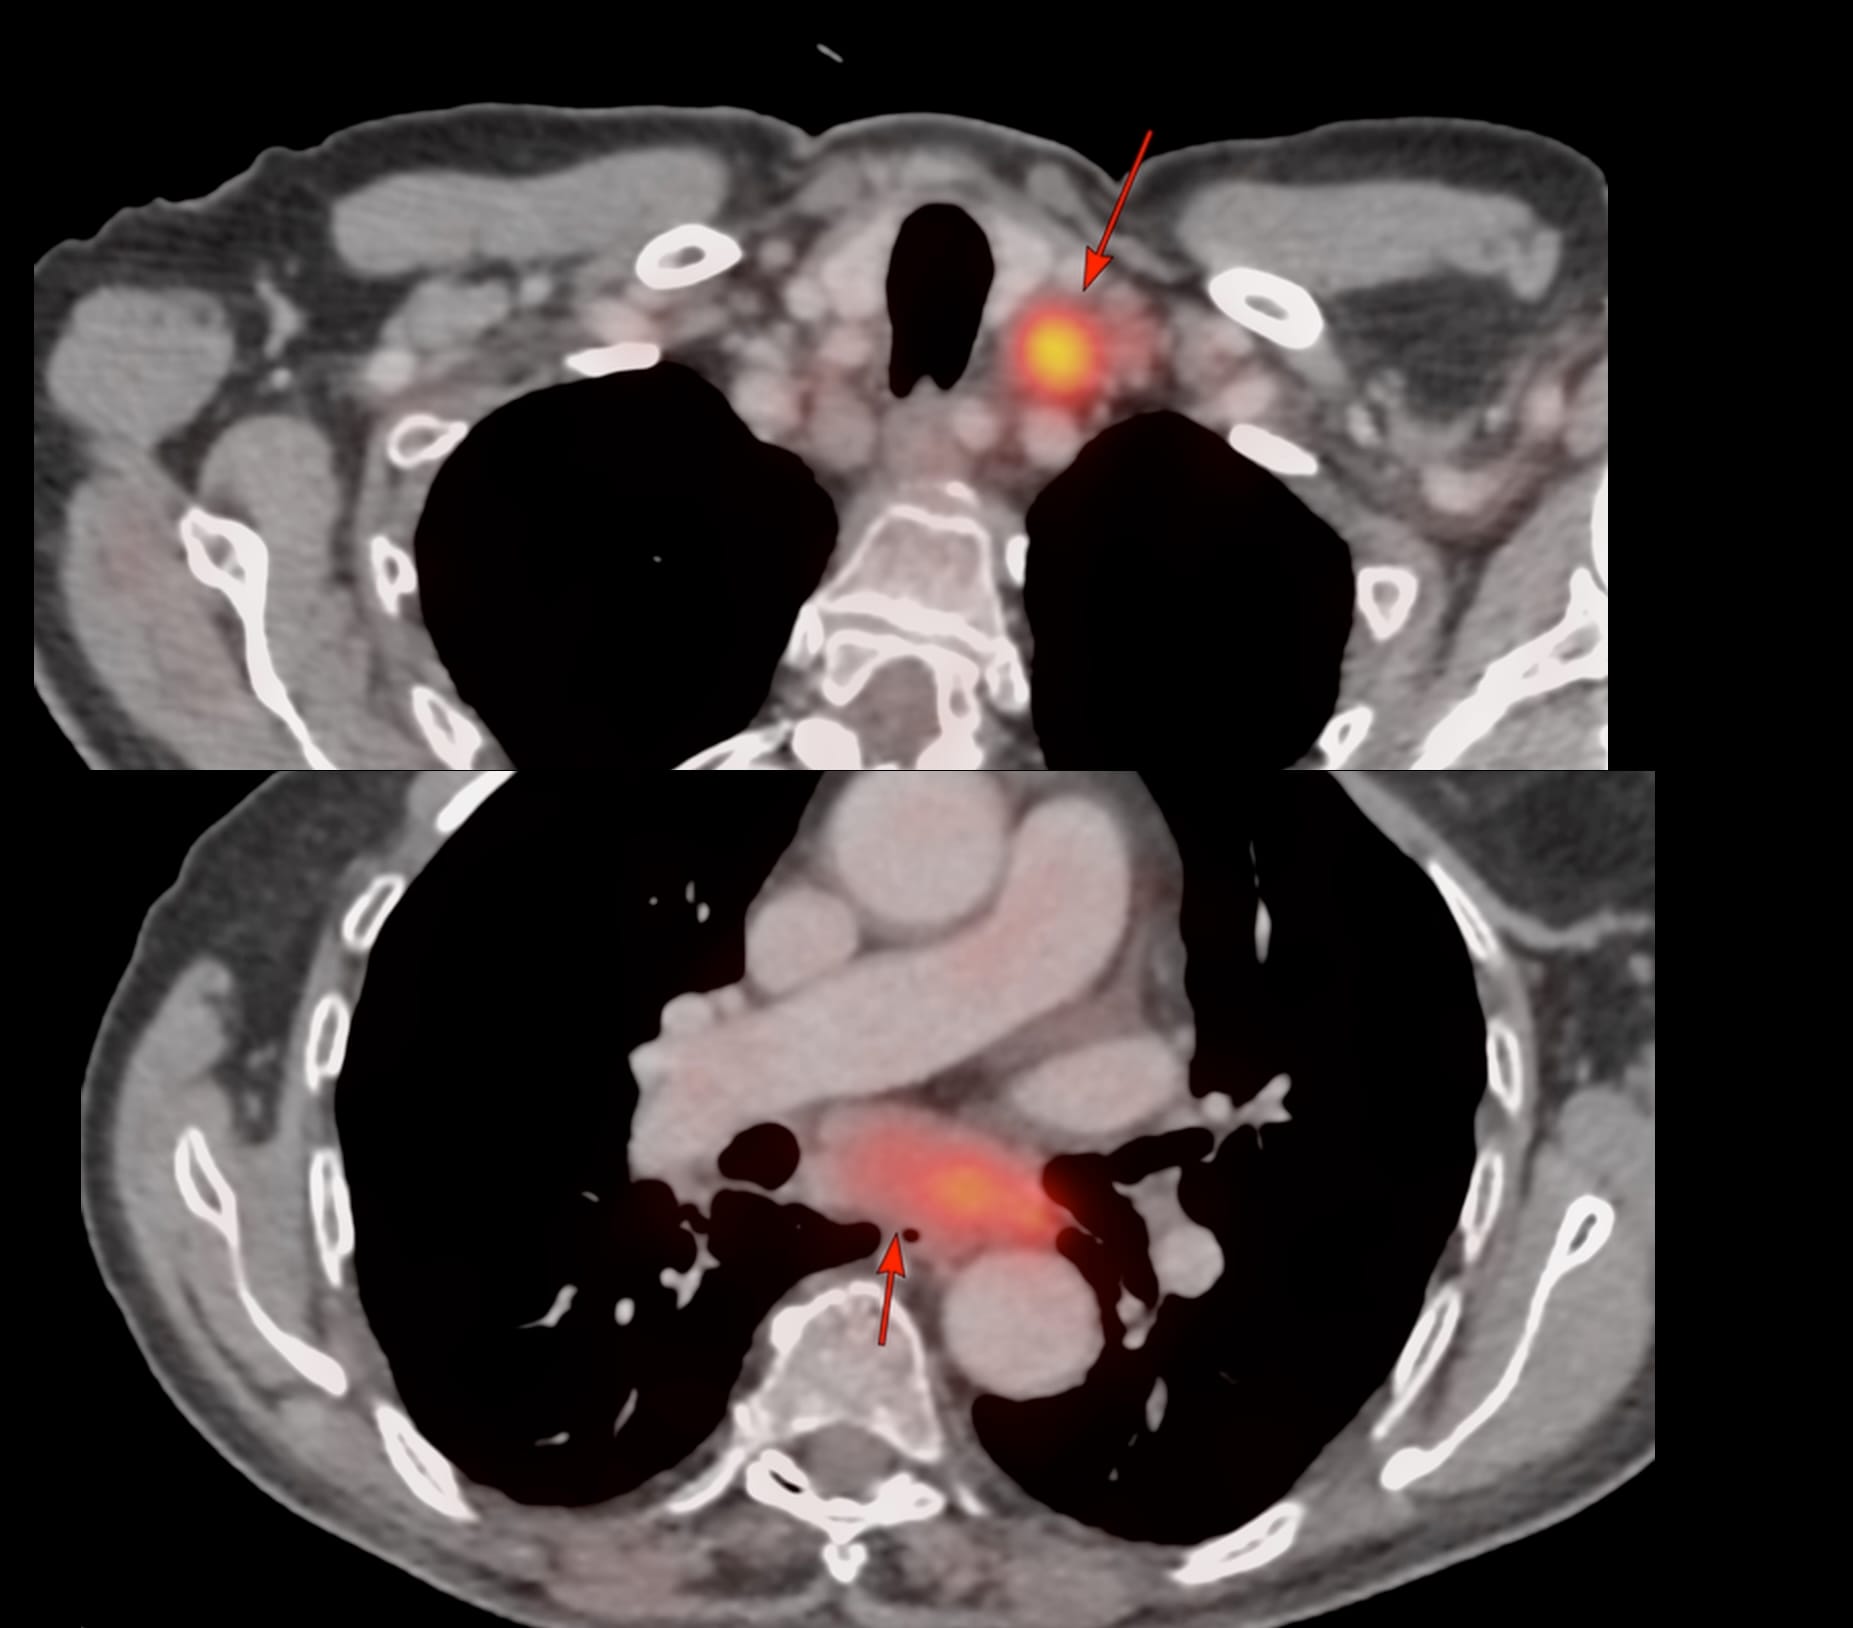

82-years old known to have T-cell non-Hodgkin's lymphoma had a PET in Jan that showed enlarged mediastinal and left supraclavicular nodes.

3 months later, he clinically worsened and CT scan showed the same nodes with mild increase in the subcarinal node size and bilateral effusions and he was referred for a CT guided biopsy of the subcarinal node. The short axis of the node was 25 mm, so biopsy was feasible.

The effusion was a concern, but in the prone position, the fluid moved anteriorly and did not come in the way, though a transeffusion or transpneumothorax biopsy is always a possibility.